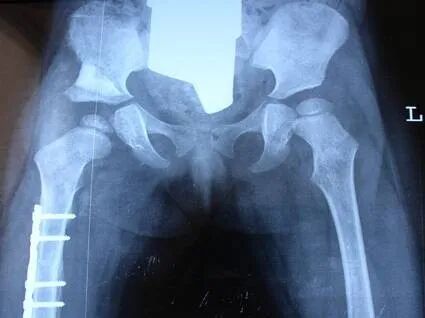

喜讯 矫形骨科专家秦泗河12月13号来合肥会诊手术 我国著名矫形骨科专家、秦泗河教授,将于2025年12月13日,到安徽合肥东南外科医院会诊手术! 马蹄内翻足 发育性髋关节脱位 学科带头人介绍 卢成 骨科主任 从事骨科临床工作二十多年,曾于2011年在清华大学附属医院师从中国著名矫形外科专家秦泗河教授学习矫形外科,积累了大量的临床诊疗经验。熟悉骨科常见病、多发病的诊断及治疗,在四肢畸形矫正及骨外固定技术领域有较深的造诣。 擅长:骨外固定及Iizarov技术治疗各种下肢畸形包括脊髓灰质炎后遗症、脑瘫肢体功能障碍、先天性髋关节脱位、膝内、外翻、先天性多发性关节挛缩症、骨缺损、骨不连、骨髓炎,以及先天性马蹄内翻足、拇外翻等各种复杂的足踝部畸形、脊柱裂后遗各种下肢畸形等。同时在成骨性肿瘤、成软骨性肿瘤、骨肉瘤等骨肿瘤疾病的治疗,股骨头坏死、颈椎病/腰椎病的手术治疗、椎体成形术、关节创伤、关节置换等方面也有颇深的造诣。 欢迎安徽省及周边地区患友积极就诊、复查。凡在安徽合肥东南外科医院就医患友,均由秦教授亲诊手术。 如您身边有先天性肢体畸形、儿麻、脑瘫等肢体运动功能障碍的患者,请不要错过与矫形大师面对面的交流和治疗机会。 联系人:卢成主任 电话:13855184363